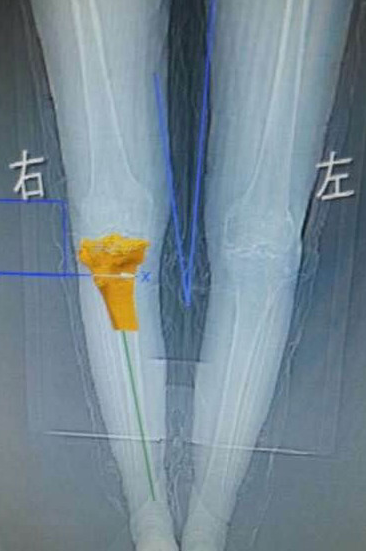

2015年2月4日,我院骨伤科(关节组)为72岁周玉枝老人成功实施了3D打印人工膝关节置换术,为她装上了“私人定制”关节。据悉,这是川南地区首例在膝关节手术中应用3D手术进行膝关节置换。

据介绍,3D打印技术运用于膝关节置换,就是通过CT扫描,把人体的骨骼、硬组织在计算机里重建,建立CAD模型后,通过3D打印出来,做成1∶1的树脂高分子模型,虽然不能直接用,但可以作为医生制定手术方案的手术导航的模板,提高手术精确性,为患者做出“私人定制”的关节模型。